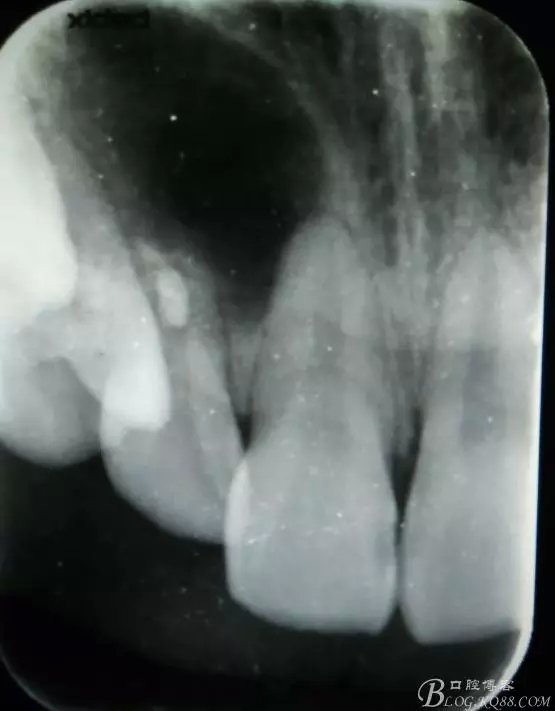

病例資料: 患者、柴xx、女、16歲。專科檢查及病歷如下圖: 患者同意我院正畸科建議,遂轉(zhuǎn)診倒外科。術(shù)前簽知情同意書。 治療過程: 圖1.術(shù)前的CBCT檢查:13阻生,疑為含牙囊腫。縱剖面顯示12牙根吸收至根尖1/3。 圖2.局部麻醉下 。行唇側(cè)弧形切口,12松動不到1°。 圖3.翻瓣、暴露骨面。 圖4.去骨、 暴露13牙冠 圖5.去骨、逐漸顯露13。 圖7.拔除13. 圖8.摘除囊壁 圖9.必須完整剝離囊壁。 圖10.摘除囊壁后形成的骨腔 圖11.超聲骨刀12根尖倒預(yù)備 圖13. 消毒棉球骨腔內(nèi)隔濕血液,紙尖干燥倒預(yù)備好的根管 圖14. 紙尖無血即可 圖15。MTA倒充填 圖16.骨腔填塞膠原蛋白海綿 圖17.拔除的13及摘除的囊壁 圖18.縫合 圖19.術(shù)后x線根尖片影像:MTA封閉根尖